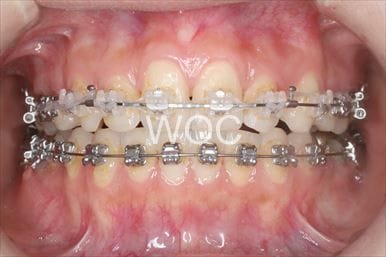

治療中1

- 年齢:20歳女性

- 主訴:出っ歯が気になる

- 基本矯正料金:120万円

- 治療期間:1年7ヶ月

- 抜歯部位:上顎両側第一小臼歯